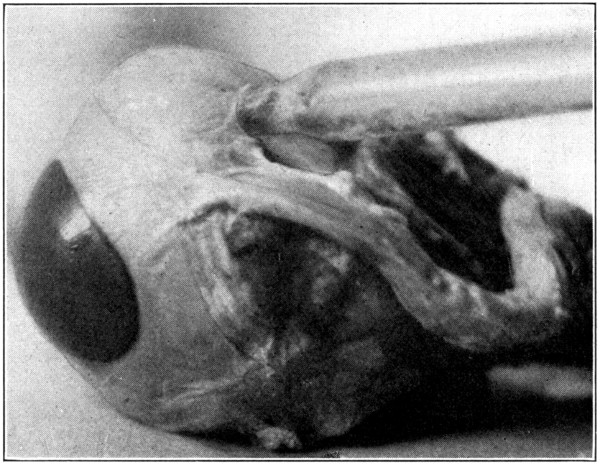

Fig. 5—Picking up the choroid with the point of the scissors.

Fig. 6—A. Hyaloid, vitreous, and lens ready to drop out of the eyeball.

Fig. 7—Photograph of dissected hyaloid membrane (A), with pigmented indentations of the ciliary processes, the suspensory ligament (B), and the crystalline lens in its capsule (C). (Page 34.)

Many times a considerable amount of pigment from the second tunic will remain attached[34] to the processus zonuloe. This pigment may be easily removed by scraping it off with the sharp edge of the scalpel or by brushing it off with a soft, wet tooth-brush.

For purposes of demonstration or study the specimen should be placed in a small bottle or a vial containing a 5 per cent. solution of formaldehyde. It can then be examined with hand lens or microscope. (Fig. 7.)